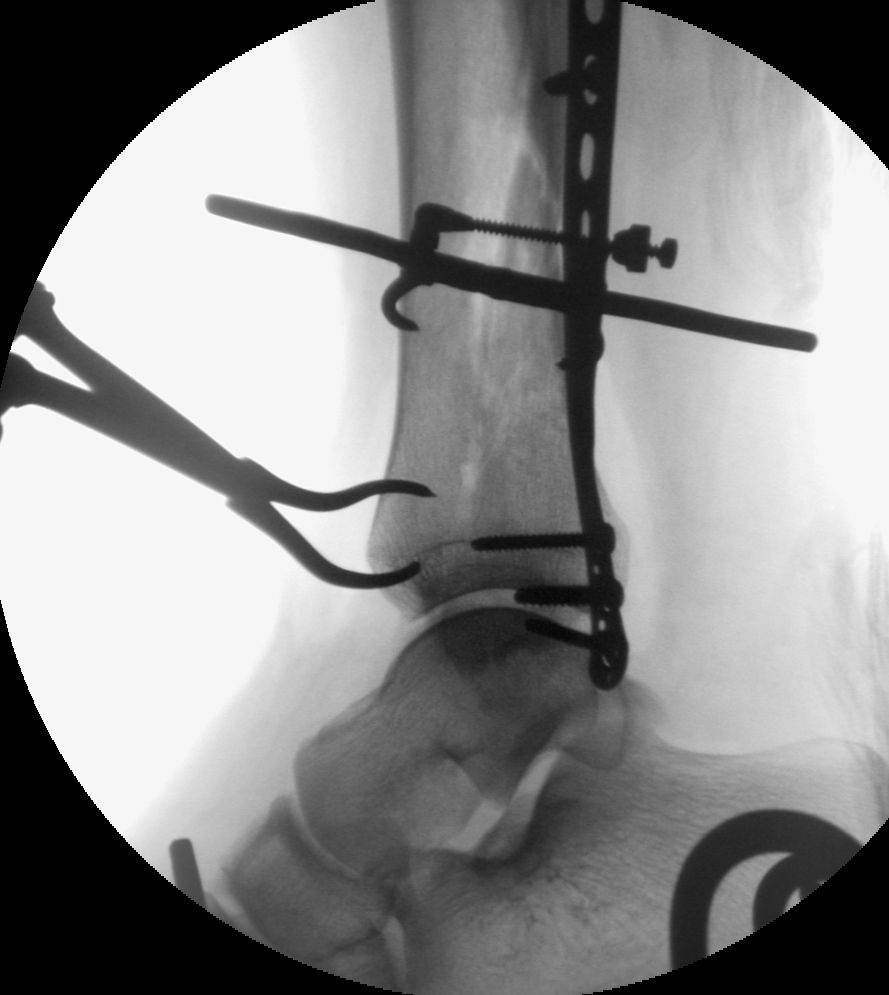

An attempted closed reduction of the shaft fracture was performed but regaining length was difficult. Given the proximity of the posteromedial approach which was used for the articular injury and the shaft fracture, this incision was simply extended proximally five additional centimeters to allow for reduction and clamp placement at the shaft fracture. No significant soft tissue dissection was performed (a, b). This allowed for atraumatic nail placement without vigorous manipulation of the reduced articular injury. The clamp was left in position distally to ensure that the distal fracture did not displace (c, d). A reamed nail was placed. The three distal interlocking screws (medial to lateral, anterior to posterior, anteromedial to posterolateral) were placed. An additional lag screw was then placed posterior to the nail to support the articular fracture reduction. A small lag screw was placed at the medial malleolus (e, f). Final radiographs demonstrate the reductions of the tibial shaft as well as the distal tibial articular injury (g, h).